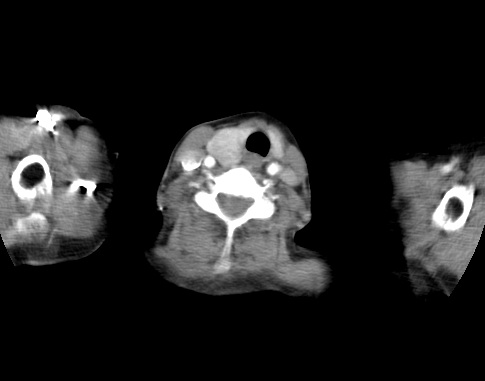

标题: CT23982:女67岁,胸部扫描时发现,甲状腺瘤? [打印本页]

标题: CT23982:女67岁,胸部扫描时发现,甲状腺瘤?

右侧甲状腺腺瘤!支持!不排除甲状腺癌可能!建议手术切除!

右侧甲状腺占位性病变,性质待定(甲状腺腺瘤?);建议:必要时行进一步检查。

右侧甲状腺占位性病变,性质待定(甲状腺腺瘤?);

右侧甲状腺占位性病变,性质待定(甲状腺腺瘤?);建议穿刺活检。

右侧甲状腺占位性病变,甲状腺腺瘤可能,建议穿刺活检。